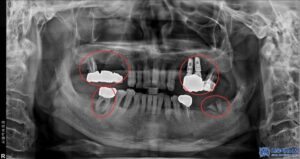

이번에 저희 서울박사치과를 찾아주신 환자분께서는

기존에 다른 치과에서 임플란트 치료를

받으셨었지만, 기존 임플란트와 보철물이

파절되면서 다시 진단을 받아보고자

저희 치과에 내원하셨습니다.

우선, 환자분의 상악 오른쪽 어금니들은

치주 염증이 심한 상태로,

기존에 받으셨던 보철물 아래로 염증이

심하게 퍼져 제거가 필요한 상태였습니다.

뿐만 아니라, 상하좌우 맨 안쪽 어금니들의

잇몸과 뼈 상태가 많이 악화되어 있어

보존이 어려운 상황이었기에

각각 발치도 진행되어야 했습니다.